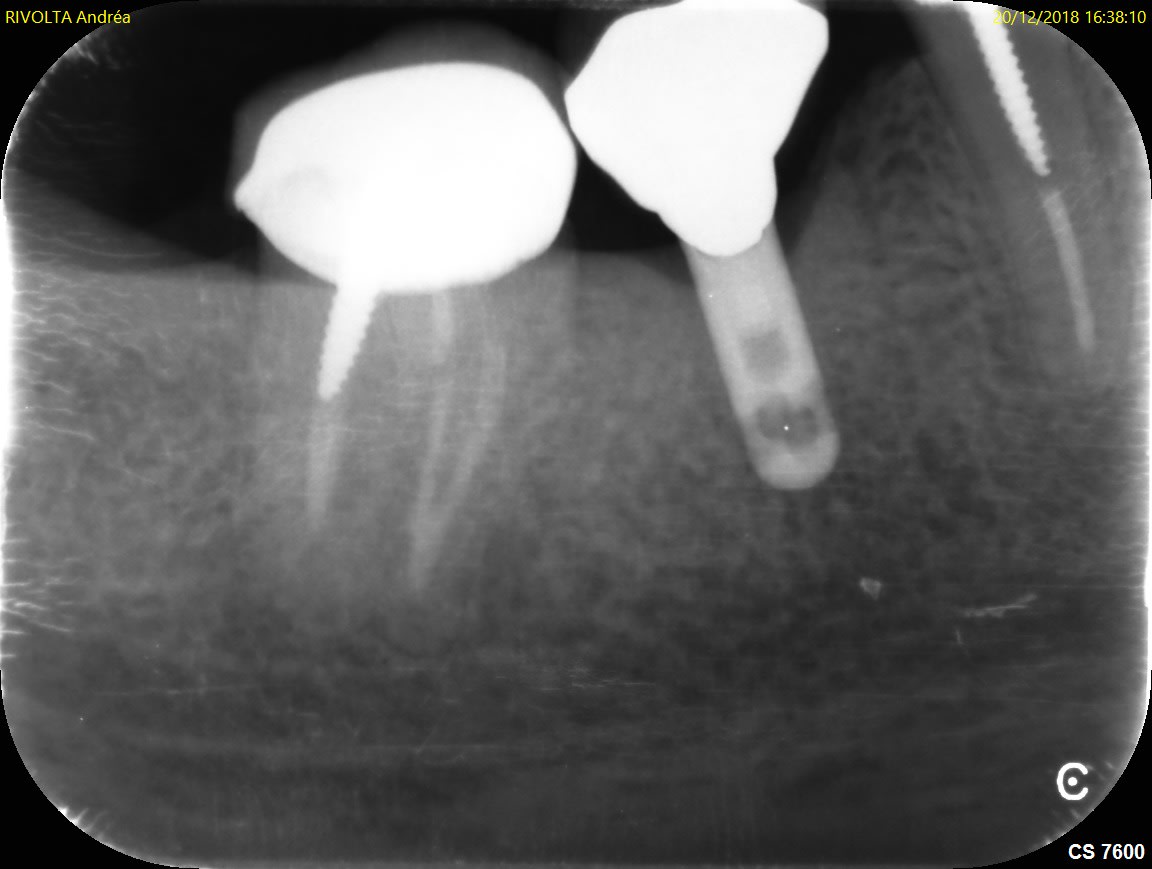

Pouvez vous m'aider à trouver la référence de l'implant ci joint.

IMZ

https://whatimplantisthat.com/implant/high-cyclinder-3/